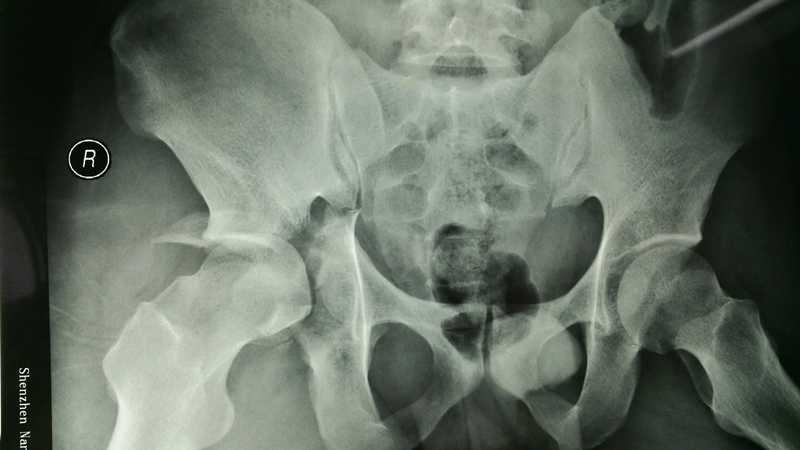

患者男性,29歲,車禍致右髖臼骨折,外院行骨折內(nèi)固定術(shù)后18個(gè)月。ct顯示:右股骨頭壞死,股骨頭上移5·8cm,髖臼后壁基本全缺損,髖臼內(nèi)壁內(nèi)移。治療分2個(gè)步驟:1,內(nèi)固定物取出,局部松解,右下肢骨牽引。2,右髖臼后壁重建,右全髖關(guān)節(jié)置換術(shù)。